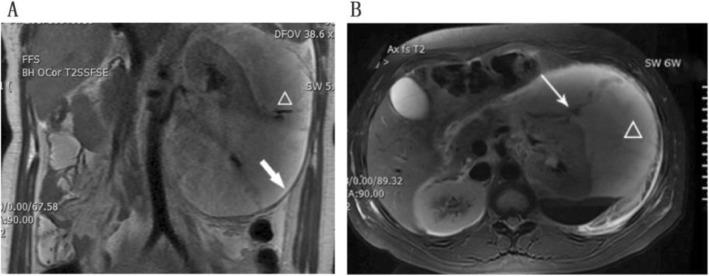

A 23-year-old primagravida was diagnosed with a spontaneous renal rupture and acute left loin pain accompanied by hematuria when she was 35 weeks pregnant. A sub-capsular perinephric cyst then developed to a size of 319 × 175 × 253 mm, and because of discomfort to the patient, we performed Cesarean section. After a healthy male newborn was delivered, fluid was suctioned from a large perirenal cyst that had an estimated size of 300 × 200 × 300 mm. A percutaneous nephrostomy tube was left in the cyst until CT showed no remaining fluid. In the six-month follow-up, the patient showed no perirenal extravasation according to an ultrasound scan, and the urine analysis and renal function tests were normal.

一位 23 岁初产妇在妊娠 35 周时被诊断为自发性肾破裂和急性左腰痛,伴有血尿。随后出现了一个包膜下肾周囊肿,大小为 319×175×253mm,由于患者不适,我们进行了剖宫产术。分娩出一个健康的男婴后,从一个估计大小为 300×200×300mm 的大肾周囊肿中吸出了液体。在囊肿中留置了经皮肾造瘘管,直到 CT 显示没有残留液体。在 6 个月的随访中,根据超声检查,患者的肾周无外渗,尿液分析和肾功能检查正常。